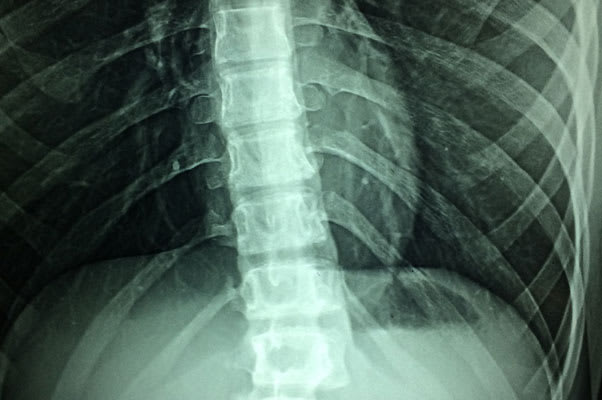

It’s called a “hot” disc for a reason. Disc herniations cause a tremendous amount of inflammation that can irritate nearby nerves and cause pain. But, did you know that inflammation is actually…a good thing? In fact, inflammation suggests a high likelihood of relief with conservative care. Confused? Well, the inflammatory process is the first step of the healing process! A disc that is “hot” or inflamed is a sign that the healing process has already begun.

New research indicates that an inflamed disc can “activate” healing throughout your immune system. Tiny blood vessels begin to form around the herniation, causing your immune system to release certain chemicals that help the disc to heal and reabsorb. What’s even more excitingis that when conservative care, such as Chiropractic, is added,researchers found that not only can the disc herniation heal, but it can completely resolve!